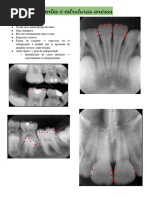

fratura radicular

1 Identificar a direção do traço de fratura.

• Traço hipodenso horizontal | vertical | oblí-

quo.

2 Quais são a(s) parede(s) envolvida(s).

• Parede palatina | vestibular | mesial | distal

3 Porção onde está localizada.

• Porção coronária | cervical | média | apical

4 Apresenta ou não reação óssea.

• Apresentando reação óssea adjacente | sem

reação óssea adjacente

5 No caso de lesão se apresenta ou não

rompimento da cortical óssea

• Rompimento da cortical óssea vestibular |

palatina | lingual

6 Apresenta ou não deslocamento do

fragmento dentário.

• Apresenta deslocamento de fragmento den-

tário na parede distal | mesial | vestibular |

palatina.

7 Fratura, fissura ou canal acessório.

• Fratura ou solução de continudade – quan-

Ruan Gabriel de Queiroz 13

do é grande e bem visível;

• Fissura – quando é pequena e discreta (geral-

mente de difícil observação);

• Canal acessório – observar a possibilidade da

imagem ser um canal acessório, ou uma rami-

ficação do conduto principal.

8 Artefato.

• Fratura: imagem se apresenta como uma li-

nha com bordas bem definidas, termina com

a estrutura dentária, sem transpassá-la, e mui-

tas vezes é fina, delicada, costuma ter conti-

nuidade ao caminhar pelo corte que está sen-

do visualizado.

• Artefato: as bordas não são tão bem defini-

das assim (aspecto de degradê, blur nas bor-

das), pode transpassar a estrutura dentária, e

costuma ser mais grossa do que uma fratura, o

artefato é mais escuro.

• Presença de material hiperdenso no dente

47, gerando artefatos na imagem, dificultan-

do a confirmação do diagnóstico de trincas e

fraturas. Sugerimos correlacionar com exame

clínico.

Exemplo 1: Presença de traço hipodenso (ra-

diolúcido) vertical (1), na parede mesial (2),

que se estende da porção cervical até a por-

ção média do elemento 23 (3), apresentan-

do reação óssea adjacente apical e na parede

mesial (4) com rompimento da cortical ves-

tibular óssea (5) e discreto deslocamento do

fragmento radicular (6). Imagem compatível

com fratura radicular (7).

Exemplo 2: Presença de discreto traço hipo-

denso (radiolúcido) oblíquo (1), na parede

distal(2), porção apical do elemento 11 (3),

apresentando reação óssea adjacente (4).

Imagem sugere fissura radicular x canal aces-

sório. Sugerimos correlacionar clinicamente.